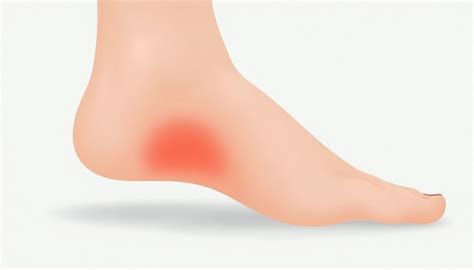

Síntomas para saber si tienes un espolón calcáneo - espolón en el talon ...